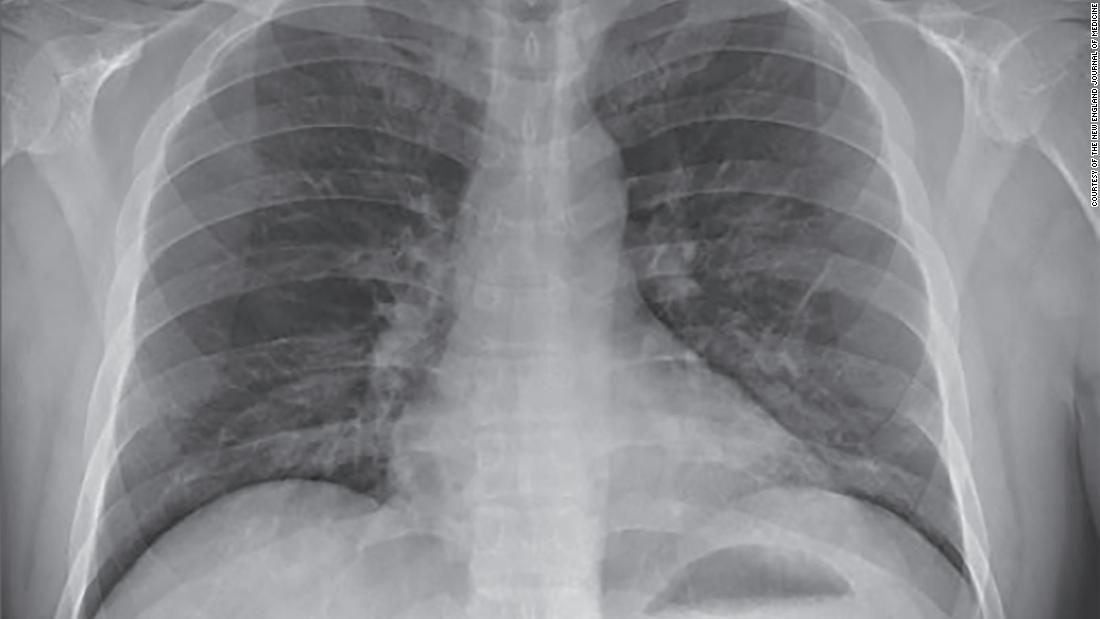

The stimulation of these extracellular and intracellular receptors by the virus also leads to the production of Type 1 Interferon which is involved with making proteins that will block the virus’ ability to manufacture its proteins. The problem in individuals that are susceptible to going into acute respiratory distress is that the pro inflammatory stimulation overwhelms the interferon’s ability to block viral protein replication. The more inflammation that takes place with the recruitment of inflammatory immune agents the more destructive for the tissue, organ, and ultimately its host. This is what happens in adult respiratory distress syndrome and it can happen very quickly.

- Acute Respiratory Distress Syndrome Taylor Thompson MD et al NEJM.org Aug 10, 2017

- Acute Respiratory Distress Syndrome: From Mechanism

To Translation by SeungHye Han and Rama K. Mallampalli

Journal of Immunology Feb 29, 2020